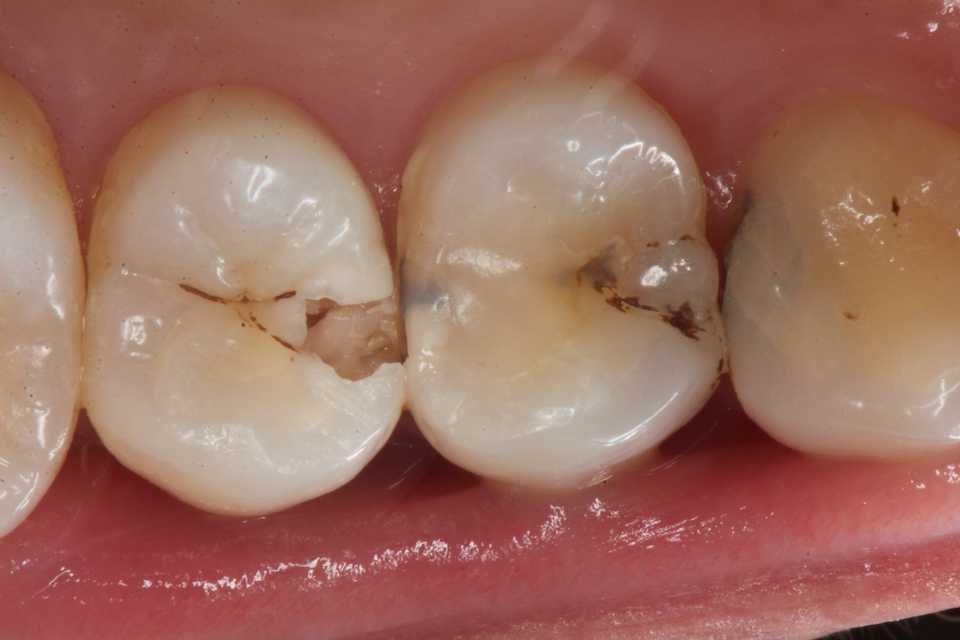

40代女性、左上5、自発痛+この方も痛くならないと来ない人。痛みが出ている歯は不可逆性の歯髄炎とか言って、治らないので通常は神経を取って被せるとか回数がかかり面倒な治療をするということになるのだが、僕にはそんな体力も、暇もない、お金も要らないとなれば、1回で終わるCRでの再建をするしかない。露髄(黄色矢印)しているのだけれど、3MIX+α-TCPで直覆すればなんにも症状は出ない。その場で痛みは消え失せる。露髄しているとか痛みが出ている歯は神経を取らないとだめ、というのは抗菌剤のなかった50年以上前の話のはずなのだが、なぜか今もやっている。多分そうしないと間がもたないとか、儲からないとか、CR再建の技術がないとか、そもそも歯学部で習っていないとか、大人の事情があるのだろうと思う。この方はデンタルフロスとか使う様な方ではないので、隣接面にフロスが通る様にはしていない。僕が使っているボンディング材はこちら。α-TCPの50%クエン酸練り。この上からCRダイレクトボンディングでカバーする。3MIXの作り方はこちら。α-TCPの入手法はこちらでは時系列でどうぞ中身(象牙質)は無い。イオン化傾向は象牙質>エナメル質>金属の順だ。この順序で溶ける。これを異種金属接触腐食という。3MIX+α-TCP1次CR次回は手前側の4番の予定